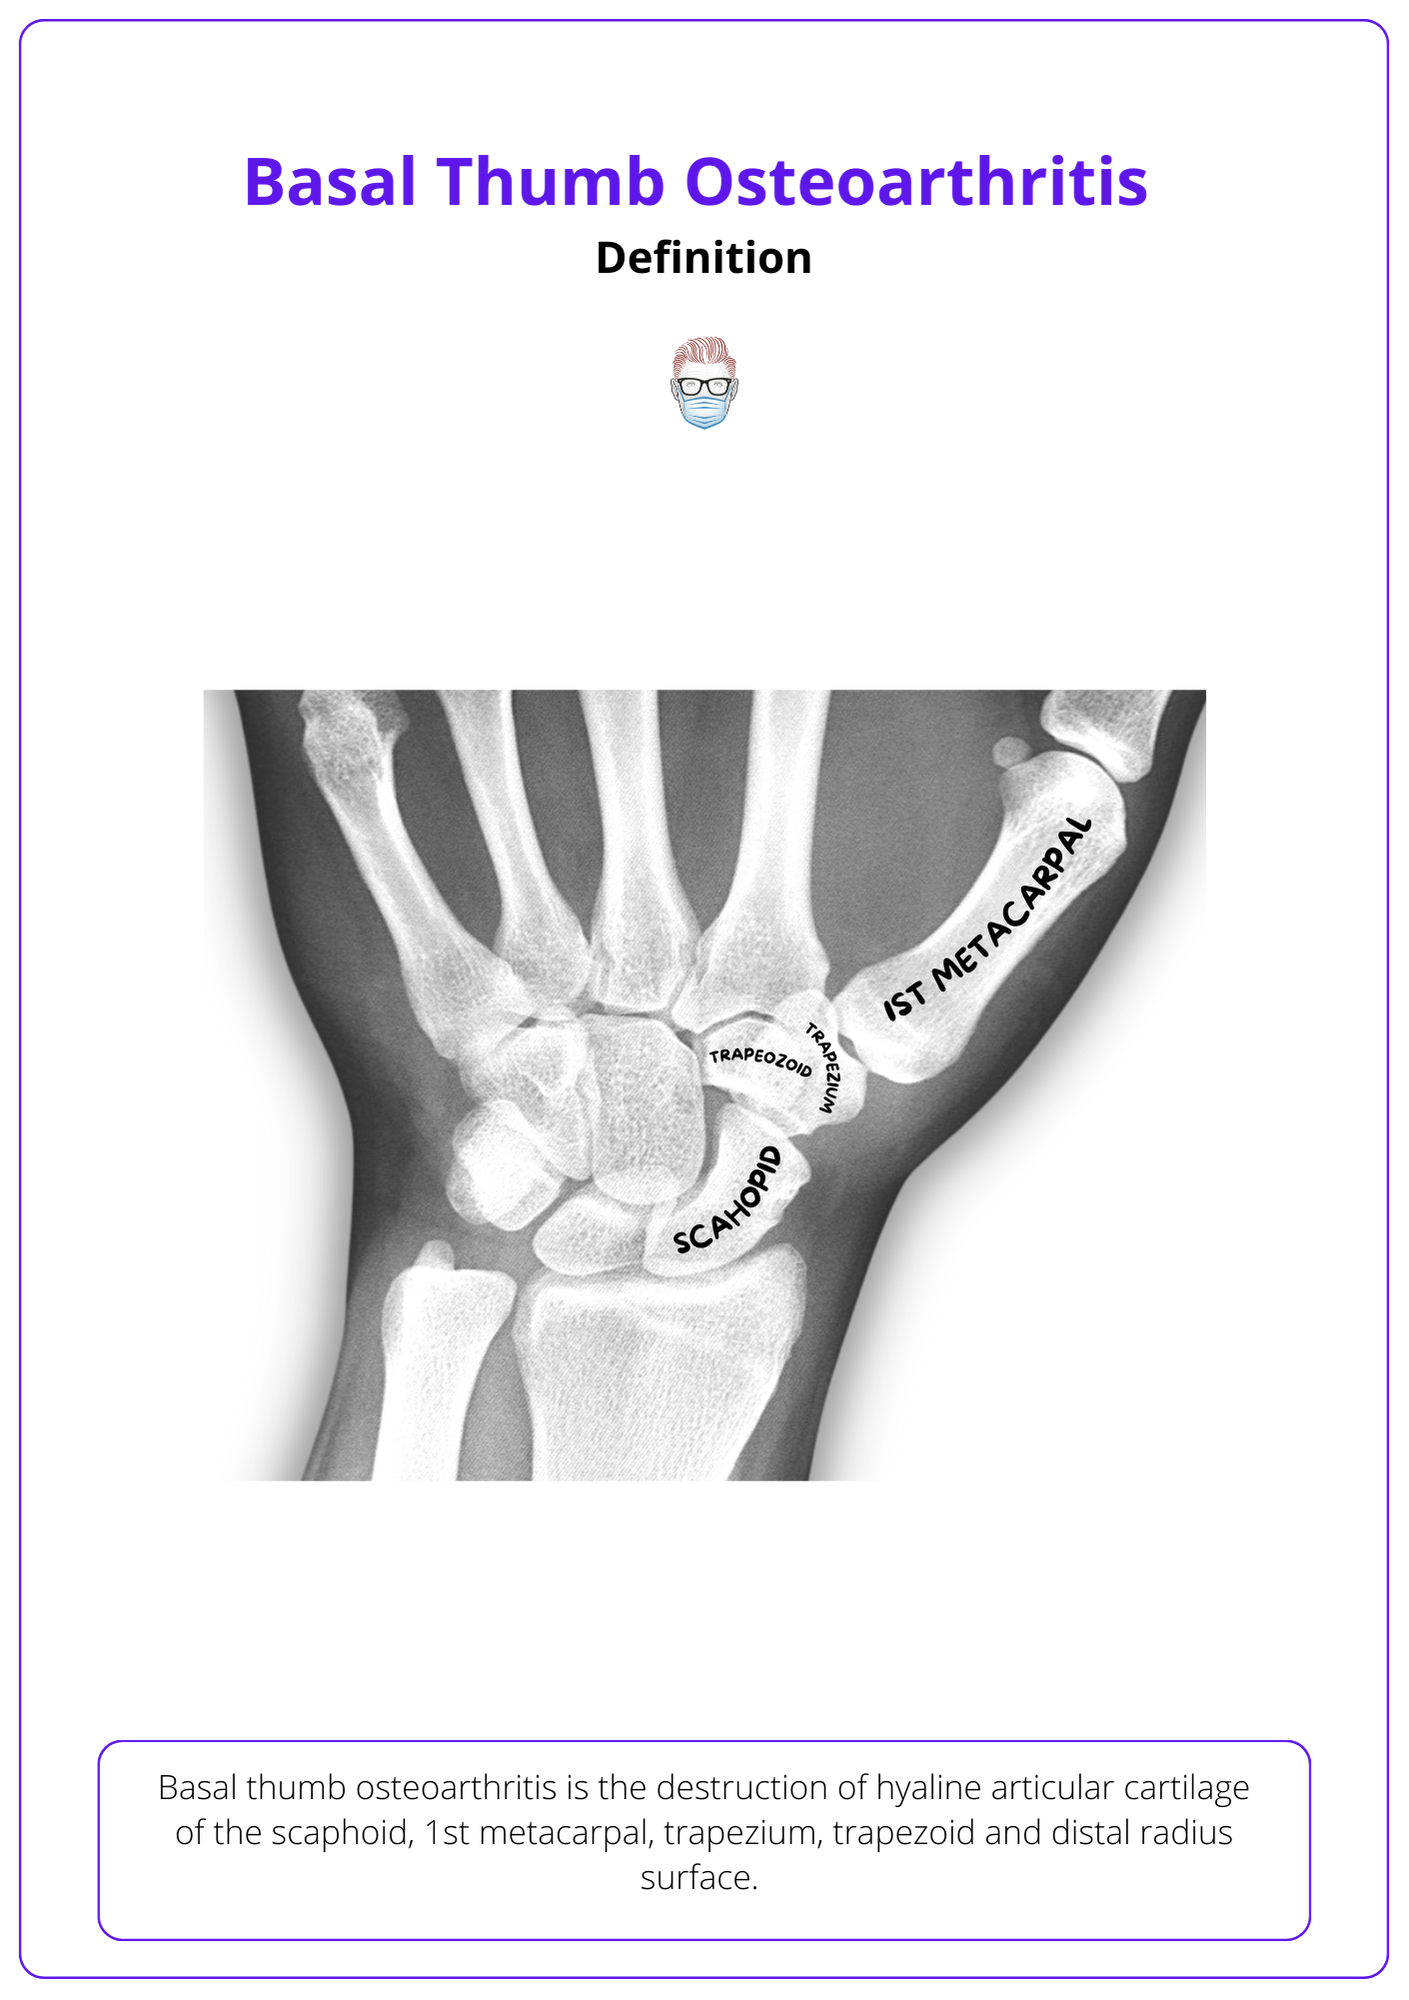

Classifying Osteoarthritis